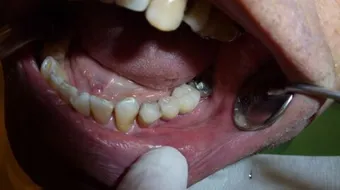

المضاعفات المبكرة لزراعة الأسنان

من الضروري اتباع تعليمات طبيب الأسنان بعد الجراحة لتقليل خطر حدوث مضاعفات، ومن التوجيهات الطبية : الحرص على تناول أغذية طرية غير صلبة، وكذلك تجنب التدخين والمحافظة على نظافة الفم والأسنان، ومن المضاعفات المحتملة بعد زراعة الأسنان نذكر ما يأتي:[2]

- عدوى في موقع الزراعة: يمكن أن تتطور العدوى أثناء وبعد الجراحة، وهناك عوامل تزيد من خطر العدوى مثل: التدخين وعدم الاهتمام بنظافة الفم.

- تحرك الزرعة: يمكن أن تحدث حركات دقيقة للزرعة عندما تفتقر غرسات الأسنان إلى الاستقرار، وعادة يحدث ذلك بعد تركيب السن الصناعي فوراً، ويجدر بالطبيب تركيب السن فوق الزرعة بعد اندماج عظم الفك بشكل صحيح مع الزرعة، لكن في بعض الأحيان يركّب الجراح السن فوراً بعد الزرع، وبهذه الطريقة يتطلب من الشخص عدداً أقل من زيارات الطبيب، لكنها قد تؤدي إلى زيادة الضغط على الزرعة وبالتالي فشل زراعة الأسنان.

- عدم وجود عظم فك كافٍ: يمكن أن تفشل المرحلة المبكرة أيضاً عندما لا يكون هناك عظام كافية لدعم زراعة الأسنان.

- رد فعل تحسسي: يحدث هذا إذا كان المريض يعاني من حساسية تجاه التيتانيوم (بالإنجليزية: Titanium)، وهو المعدن المصنوع منه الزرعات، وتشمل أعراض وعلامات الحساسية التورم، وفقدان التذوق، والإحساس بالوخز.